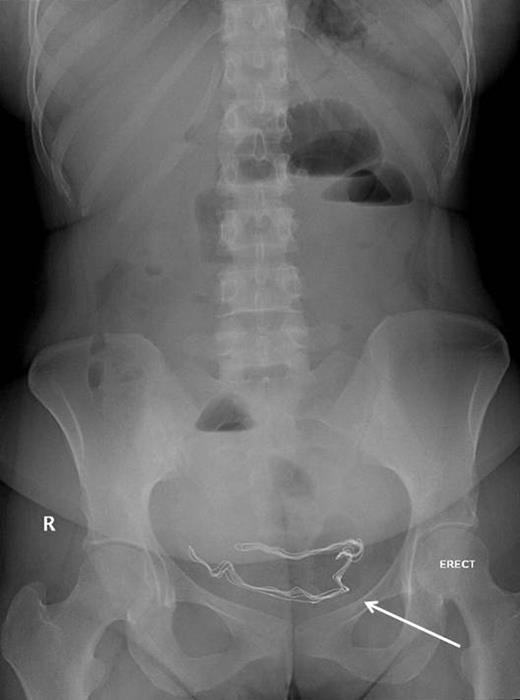

29-year-old woman was referred by her gynecologist with a history of diffuse colicky abdominal pain, nausea, repeated vomiting, constipation and progressive abdominal distention for 7 days prior to hospitalization. She had undergone an emergency cesarean section 9 months previously at a private hospital and since that time she had been complaining of recurrent attacks of nonspecific abdominal pain and occasional episodes of vomiting especially after heavy meals from which she had lost 10 kg since delivery. The patient had attended emergency departments at different institutions with similar complaints and had been discharged home after each occassion, but her symptoms passed undiagnosed. Five days prior to admission, abdominal roentography was done at an emergency department for her abdominal complaint, which showed radio-opaque density in the pelvis (Fig. 1), but it was mistakenly overlooked and she was discharged home with a diagnosis of nonspecific abdominal pain.

Proximal small intestinal dilatation with the radio-opaque mark migrated proximally to the abdomen (arrow), indicating its mobile nature.